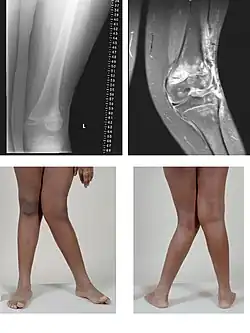

| Valgus deformity of the knee (genu valgum), seen in MRI and photograph | |

- Knee: genu valgum (from Latin genu = knee) – the tibia is turned outward in relation to the femur, resulting in a "knock-kneed" appearance. Common causes of knock-knee in adults include arthritis of the knee and traumatic injuries.